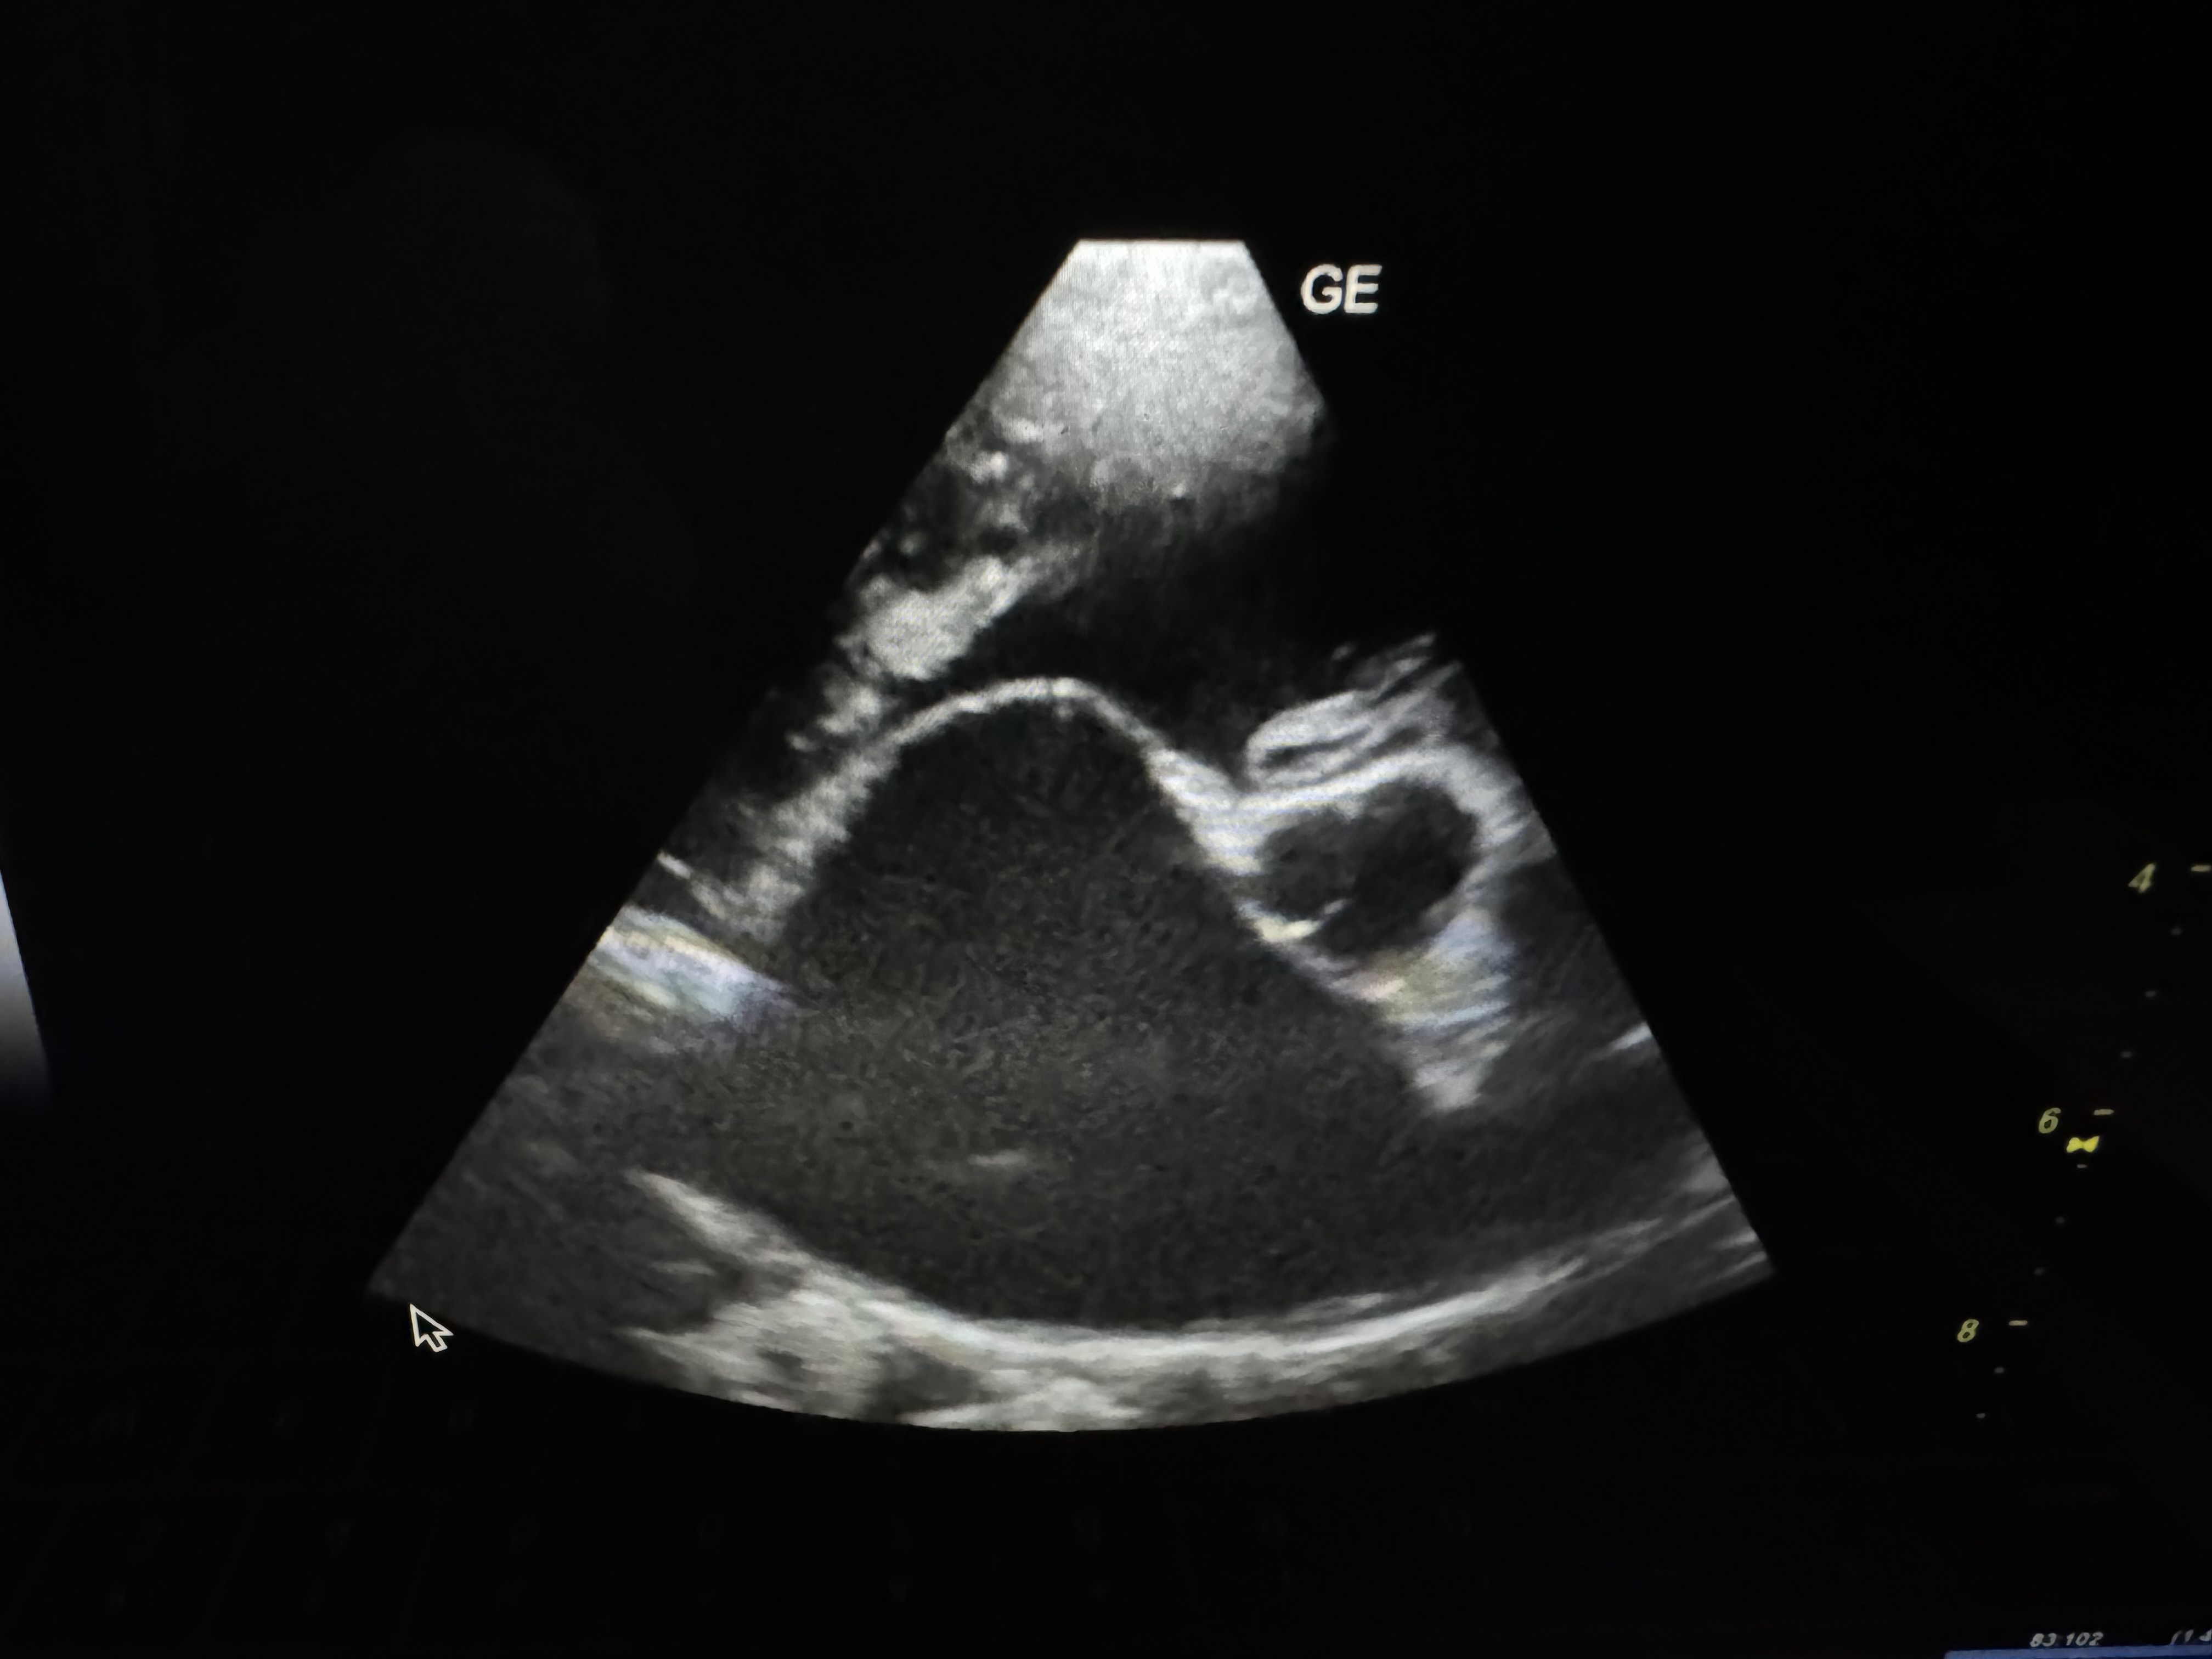

Delve into the pathogenesis of thromboembolic disease in cats with our comprehensive 1 hour CE. Learn about risk factors, prevention strategies, and various treatment options. Join Dr. Rebecca Saunders, DACVIM (Cardiology) to gain valuable insights and confidence in managing these tough cases. Many of them can survive and have a good quality of life after treatment!

Aortic Thromboembolism